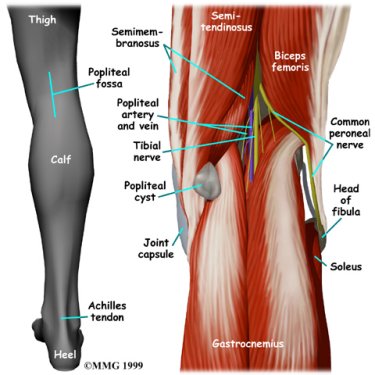

A popliteal cyst is a small, bag-like structure that forms when the joint lining produces too much fluid in the knee. The extra fluid builds up and pushes through the back part of the joint capsule, forming a cyst. The cyst squeezes out toward the back part of the knee in the area called the popliteal fossa, the indentation felt in the back part of the knee between the two hamstring tendons and the top part of the calf muscle.

Popliteal Fossa

Most people will be able to feel the cyst in the hollow area right behind the knee joint.

A popliteal cyst forms very near the major nerve and blood vessels of the leg. It is possible that these structures can be injured during surgery.

If an injury happens, it can be a serious complication. Injury to the nerves can cause numbness or weakness in the foot and lower leg. Injury to the blood vessels may require surgery to repair them.